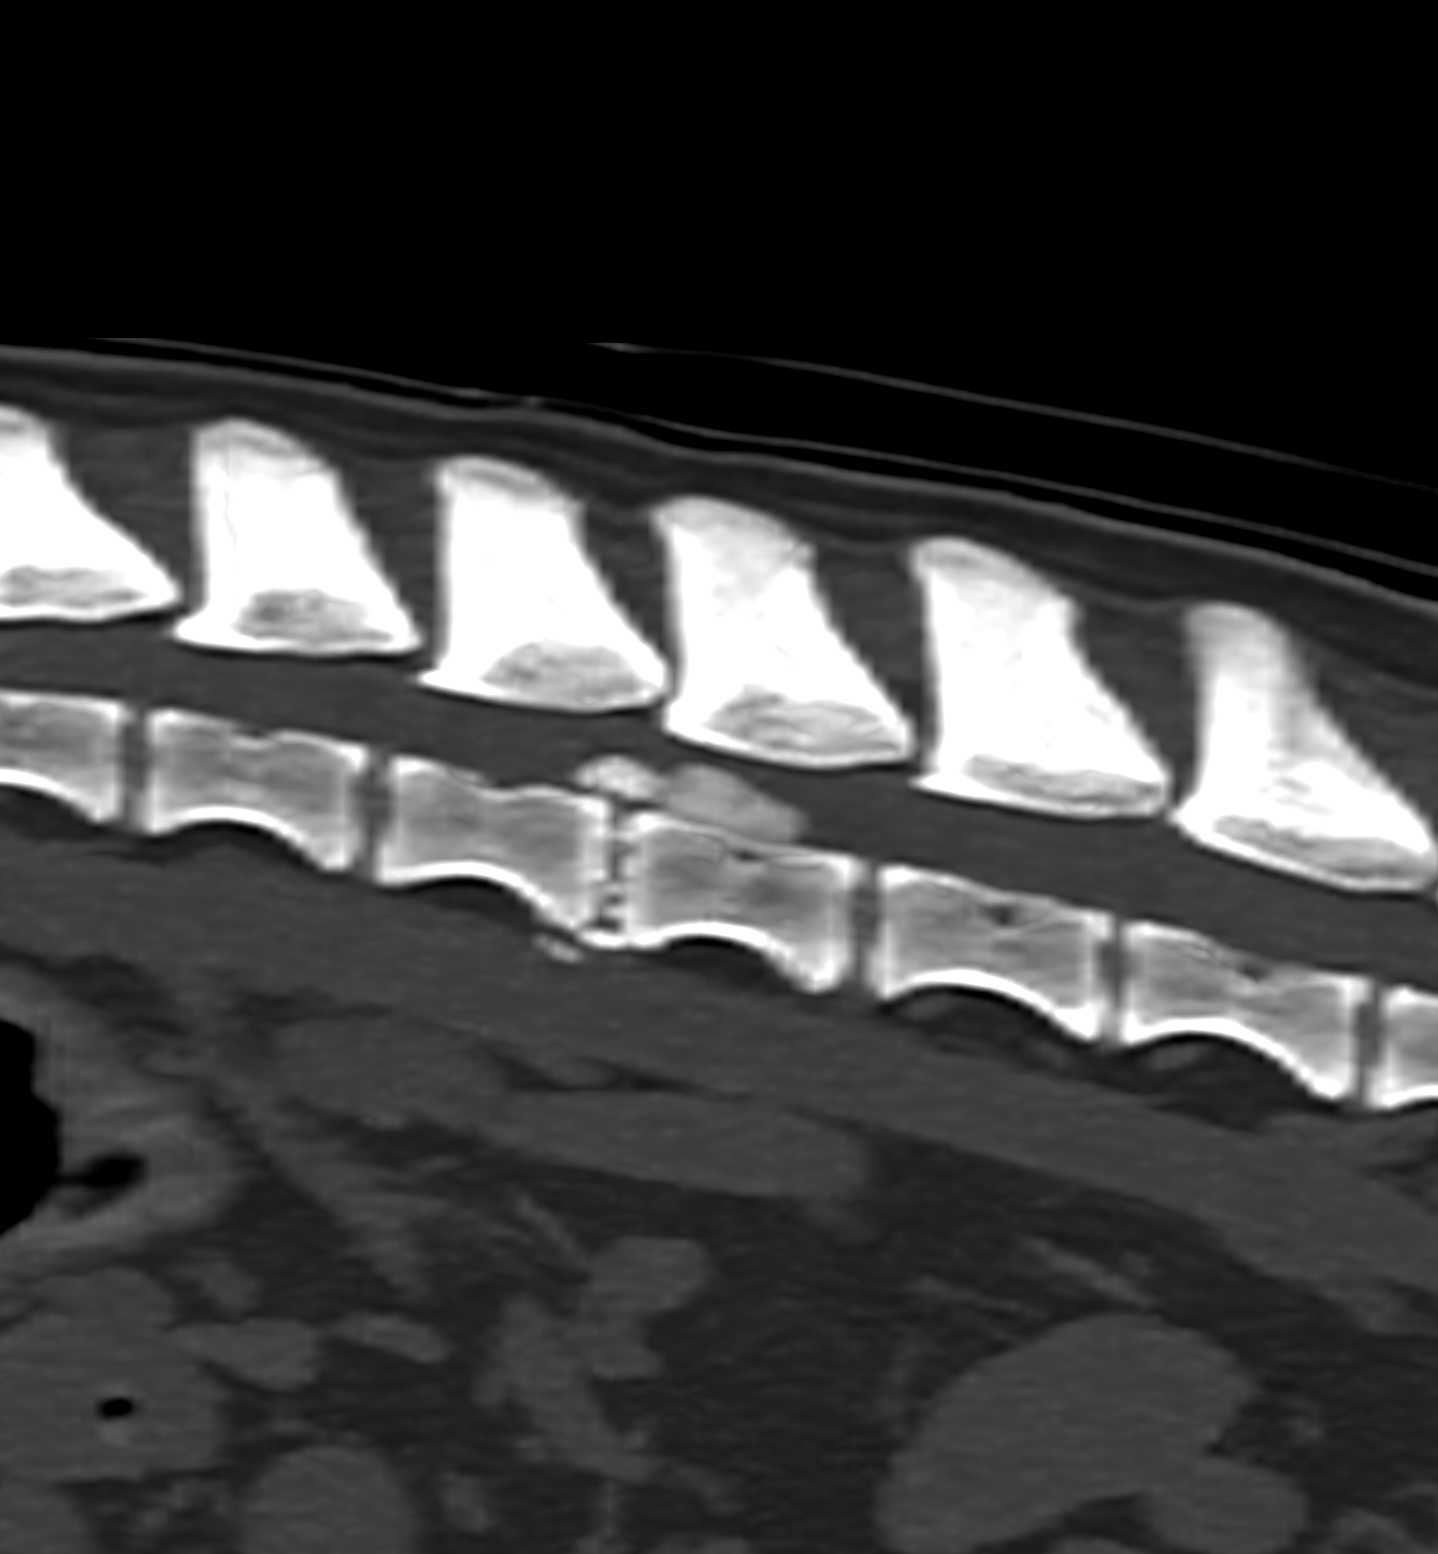

Advanced imaging and specialist investigations are often required to establish a neurological diagnosis. These may include CT, MRI or cerebrospinal fluid sampling and are arranged at trusted partner hospitals with appropriate facilities for neurological patients.